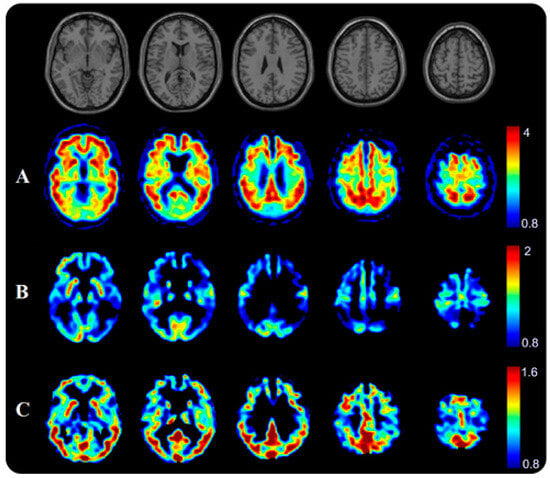

- Yousefzadeh-Nowshahr, E.; Winter, G.; Bohn, P.; Kneer, K.; von Arnim, C.A.F.; Otto, M.; Solbach, C.; Anderl-Straub, S.; Polivka, D.; Fissler, P.; et al. Quantitative analysis of regional distribution of tau pathology with 11C-PBB3-PET in a clinical setting. PLoS ONE 2022, 17, e0266906. [Google Scholar] [CrossRef]

- Yousefzadeh-Nowshahr, E.; Winter, G.; Bohn, P.; Kneer, K.; von Arnim, C.A.F.; Otto, M.; Solbach, C.; Anderl-Straub, S.; Polivka, D.; Fissler, P.; et al. Comparison of MRI-based and PET-based image pre-processing for quantification of 11C-PBB3 uptake in human brain. Z. Fur Med. Phys. 2021, 31, 37–47. [Google Scholar] [CrossRef] [PubMed]

- Shimada, H.; Kitamura, S.; Shinotoh, H.; Endo, H.; Niwa, F.; Hirano, S.; Kimura, Y.; Zhang, M.R.; Kuwabara, S.; Suhara, T.; et al. Association between Abeta and tau accumulations and their influence on clinical features in aging and Alzheimer’s disease spectrum brains: A [11C]PBB3-PET study. Alzheimer’s Dement. 2017, 6, 11–20. [Google Scholar] [CrossRef]